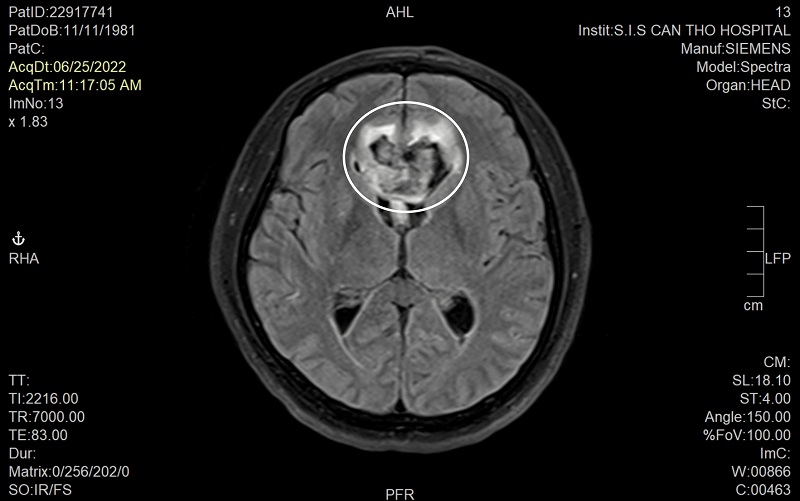

Hình ảnh MRI cho thấy túi phình mạch máu bị vỡ của bệnh nhân T.V.H khá lớn và ở vị trí nguy hiểm. Ảnh: BVCC Khi vào đến khoa cấp cứu, các bác sĩ tại bệnh viện Đa khoa Quốc tế S.I.S Cần Thơ nhanh chóng tiếp nhận và tiến hành đo huyết áp, cho bệnh nhân thở oxy và chụp MRI để xác định nguyên nhân gây đột quỵ và hôn mê. Sau khoảng 10 phút chụp MRI mạch máu não các bác sĩ đã phát hiện ngay bệnh nhân đã bị vỡ túi phình mạch máu não vị trí động mạch thông trước rất phức tạp… TS.BS Trần Chí Cường – Giám đốc bệnh viện trực tiếp thực hiện ca can thiệp cho biết: “Đây là trường hợp rất hi hữu được cứu sống. Vì bệnh nhân H. xuất hiện triệu chứng đau đầu đột ngột dữ dội, co giật, hôn mê sau đó lại tỉnh dậy và lặp lại 3 lần như vậy… Khả năng mỗi lần bệnh nhân lên cơn co giật hôn mê là rơi vào tình trạng đợt xuất huyết não từ túi phình vỡ ra. Thông thường, các trường hợp bệnh nhân xuất huyết do vỡ túi phình nguy cơ tử vong do vỡ lần đầu là khoảng 30-50% tùy theo lượng máu chảy, lần 2-3 nguy cơ tử vong tăng lên 80-90%”.

Hình ảnh MRI cho thấy túi phình mạch máu bị vỡ của bệnh nhân T.V.H khá lớn và ở vị trí nguy hiểm. Ảnh: BVCC Khi vào đến khoa cấp cứu, các bác sĩ tại bệnh viện Đa khoa Quốc tế S.I.S Cần Thơ nhanh chóng tiếp nhận và tiến hành đo huyết áp, cho bệnh nhân thở oxy và chụp MRI để xác định nguyên nhân gây đột quỵ và hôn mê. Sau khoảng 10 phút chụp MRI mạch máu não các bác sĩ đã phát hiện ngay bệnh nhân đã bị vỡ túi phình mạch máu não vị trí động mạch thông trước rất phức tạp… TS.BS Trần Chí Cường – Giám đốc bệnh viện trực tiếp thực hiện ca can thiệp cho biết: “Đây là trường hợp rất hi hữu được cứu sống. Vì bệnh nhân H. xuất hiện triệu chứng đau đầu đột ngột dữ dội, co giật, hôn mê sau đó lại tỉnh dậy và lặp lại 3 lần như vậy… Khả năng mỗi lần bệnh nhân lên cơn co giật hôn mê là rơi vào tình trạng đợt xuất huyết não từ túi phình vỡ ra. Thông thường, các trường hợp bệnh nhân xuất huyết do vỡ túi phình nguy cơ tử vong do vỡ lần đầu là khoảng 30-50% tùy theo lượng máu chảy, lần 2-3 nguy cơ tử vong tăng lên 80-90%”. Bệnh nhân H. đã được can thiệp đặt coil thành công. Ảnh: BVCC Phương pháp điều trị phình mạch máu não vỡ bao gồm phẫu thuật kẹp túi phình và can thiệp nội mạch DSA đặt coils. Theo nhiều nghiên cứu trên thế giới can thiệp nội mạch DSA thì an toàn hơn và ít xâm lấn. “Với can thiệp nội mạch DSA có thể đặt coils đơn thuần khi túi phình cổ hẹp, khi túi phình cổ rộng đang xuất huyết như bệnh nhân H. kỹ thuật can thiệp vô cùng khó khăn vì phải dùng stent che cổ túi rồi sau đó mới đặt coil được. Tuy nhiên vấn đề là nguy cơ tắc stent cấp vì bệnh nhân không thể uống thuốc chống tắc stent trong lúc này” – BS Cường giải thích. “Với những khó khăn như thế, ekip chúng tôi đã dùng kỹ thuật tạo hình cổ túi phình lúc đặt coils bằng stent lấy huyết khối, khi đặt coils xong cầm máu được chúng tôi tiến hành kéo stent ra và bệnh nhân không cần dùng thuốc chống đông sau đó” – BS.CK2 Ngô Minh Tuấn người cùng thực hiện thủ thuật chia sẻ thêm. Chị Thủy tâm sự: “Khi bác sĩ ra ngoài báo can thiệp thành công tôi vô cùng vui mừng. Tôi nghĩ chồng tôi được phù hộ và có một phép màu nào đó chứ không là không thể qua được. Bác sĩ Cường rất nhiệt tình, giản dị, thân thuộc như người trong gia đình vậy. Do đó, tôi vô cùng biết ơn, nhờ có bác sĩ Cường mà chồng tôi đã được cứu sống. Nhưng nếu biết sớm thì gia đình tôi đã đưa chồng đến bệnh viện S.I.S cấp cứu…”